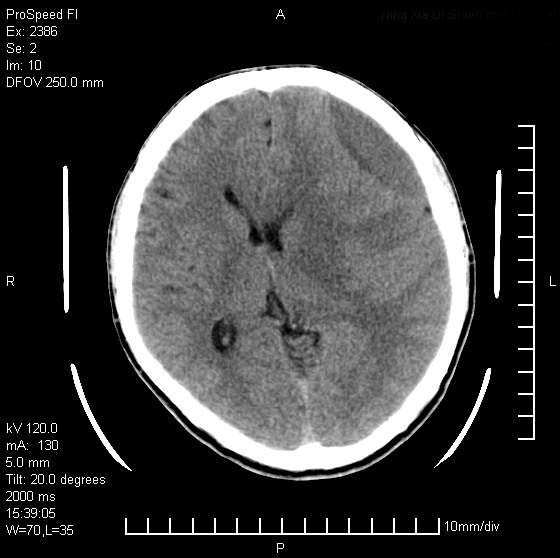

以下是引用天南地北在2007-9-19 18:43:00的发言:[br]典型慢性硬膜外血肿[br][br][本贴已被 天南地北 于 2007-9-19 18:44:11 修改过]

以下是引用曼一拍在2007-9-20 11:06:00的发言:[br]支持慢性硬膜下血肿.[br]慢性硬膜下积液:血肿有包膜,ct值稍高于脑脊液,增强可有染色。不典型者血肿可多呈梭形.是硬脑膜与蛛网膜之间的潜在腔隙内的血肿。[br]鉴别:[br]1\\硬膜外血肿:是颅脑外伤后脑膜或板障内血管破裂,血液在颅骨与硬膜之间积聚所致.通常是脑膜动脉破裂,也可因静脉窦破裂或颅骨的板障静脉出血,发生于外伤的着力部,常与颅骨骨折并存。脑膜动脉出血则急,若是板障静脉出血在则可有慢性。[br]2\\硬膜下积液:(硬膜下水瘤)[br]是由于蛛网膜破裂,脑脊液经蛛网膜破口进入硬膜下腔不能回流。或水肿阻塞而形成。[br]ct表现:颅骨内板下方新月形低密度区近似脑脊液密度;占位效应清,周围无脑水肿。[br]